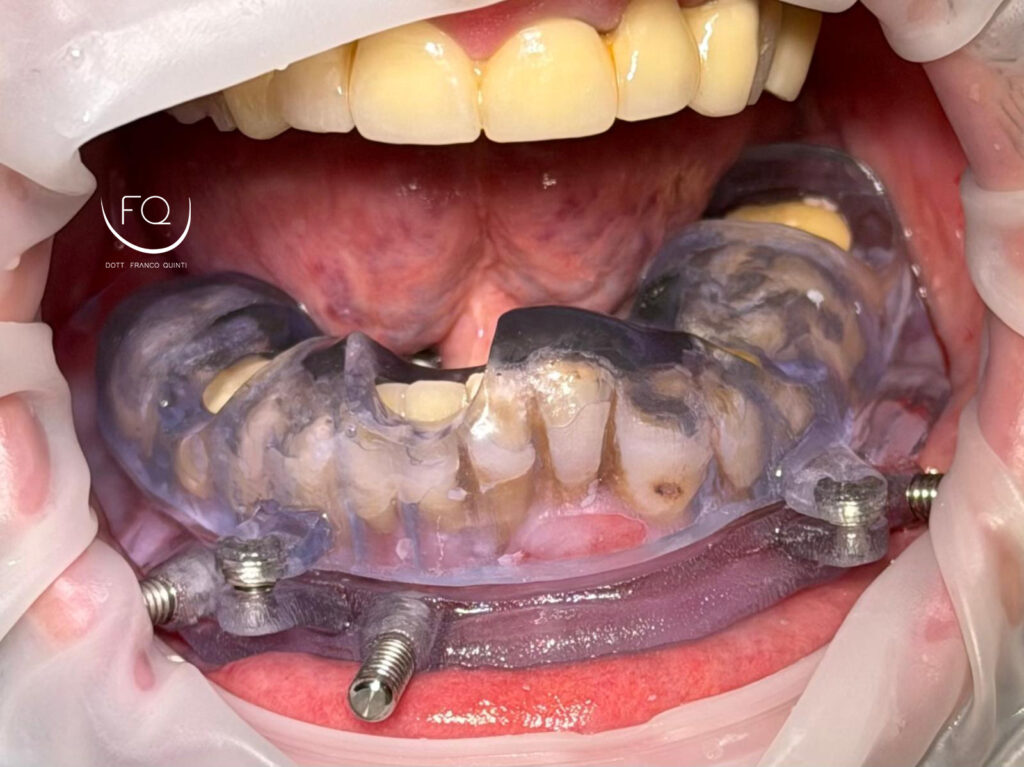

Oggi vi presento un caso di chirurgia computer guidata eseguito con Dima scomponibile.

Dall’immagine iniziale è possibile apprezzare l’estrusione del gruppo incisivo inferiore il quale è stato corretta con la protesi provvisoria a carico immediato stampata in 3D.